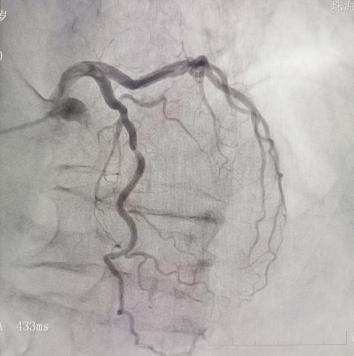

案例2

冠脉造影提示LAD中段70%左右狭窄,FFR检测结果为0.88,大于0.8,选择先采取药物治疗,定期随访。